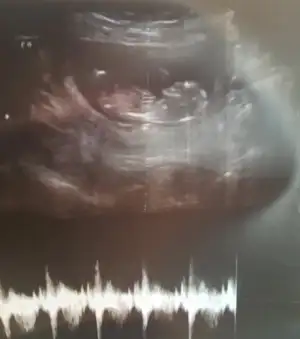

Kıza benzettim ben canımKızlar nasipse bende mart annesi olacağım. Son adet tarihime göre 12+0 haftalık ama bugün ikili tarama için gittim 12+4 haftalık çıktı bunlarda görüntüleri. Sizce cinsiyeti nedir nub anlayan var mı

Pek emin olamadım ama erkek gibi geldi, sağlıkla gelsin inşallahKızlar nasipse bende mart annesi olacağım. Son adet tarihime göre 12+0 haftalık ama bugün ikili tarama için gittim 12+4 haftalık çıktı bunlarda görüntüleri. Sizce cinsiyeti nedir nub anlayan var mı